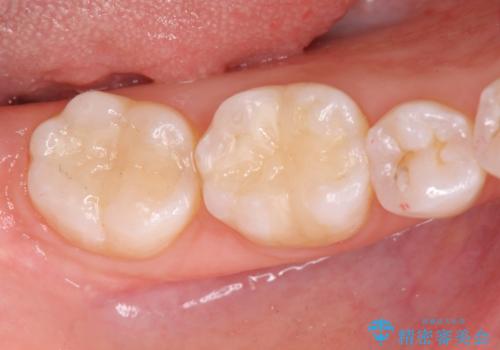

審美性を回復し、虫歯も予防のできる精密なセラミックインレーを装着することができました。